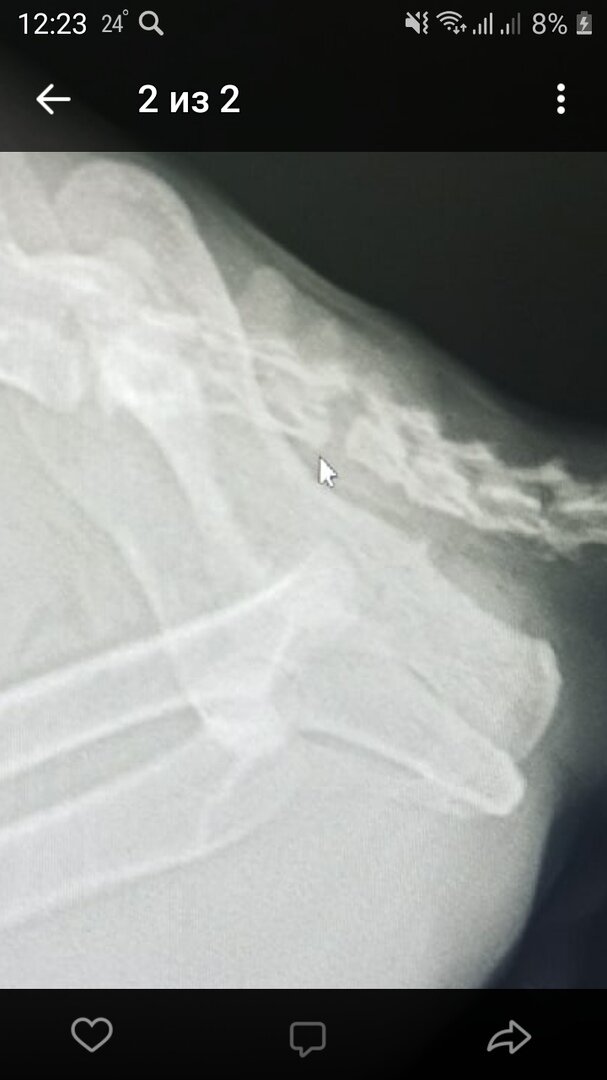

Сюрприз на рентгене

У Сени оторван хвост, очень высоко, нарушены нервы.

Котику была сделана операция и назначена послеоперационная терапия.